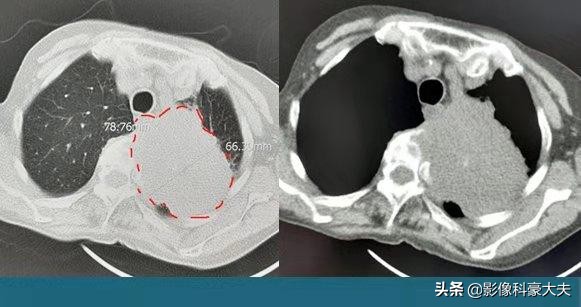

这位老人是中心型肺癌,因为发现比较早,癌细胞局限在做肺下叶支气管,做的左肺下叶完整切除,目前5年多了没有复发。有些中心型肺癌侵犯肺门重要结构,需要扩大切除,比如做一侧肺全切。还有些无法切除,就只能保守治疗了。